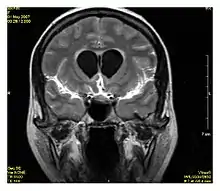

La recuperación de la inversión atenuada de fluido (FLAIR, del inglés: FLuid-Attenuated Inversion Recovery) es una secuencia de resonancia magnética con una recuperación de la inversión que neutraliza los fluidos. Por ejemplo, se puede usar en imágenes cerebrales para suprimir los efectos del líquido cefalorraquídeo (LCR) con el fin de resaltar las lesiones hiperintensas periventriculares, como las placas de esclerosis múltiple (EM).[1] Esta secuencia fue desarrollada por el Dr. Graeme Bydder. Puede usarse tanto con imágenes tridimensionales (3D FLAIR) como bidimensionales (2D FLAIR).

Imagen de RM en secuencia FLAIR que demuestra infiltración relacionada con tumor que involucra núcleos lenticulares (Flecha).

Imagen de RM en secuencia FLAIR que demuestra la infiltración relacionada con el tumor que afecta tanto a los lóbulos temporales (flecha corta) como a la sustancia negra (flecha larga).